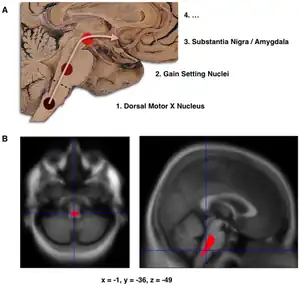

Composite of three images, one in top row (referred to in caption as A), two in second row (referred to as B). Top shows a mid-line sagittal plane of the brainstem and cerebellum. There are three circles superimposed along the brainstem and an arrow linking them from bottom to top and continuing upward and forward towards the frontal lobes of the brain. A line of text accompanies each circle: lower is "1. Dorsal Motor X Nucleus", middle is "2. Gain Setting Nuclei" and upper is "3. Substantia Nigra/Amygdala". The fourth line of text above the others says "4. ...". The two images at the bottom of the composite are magnetic resonance imaging (MRI) scans, one sagittal and the other transverse, centred at the same brain coordinates (x=-1, y=-36, z=-49). A colored blob marking volume reduction covers most of the brainstem.

1. Schematic initial progression of Lewy body deposits in the first stages of Parkinson's disease, as proposed by Braak and colleagues

2. Localization of the area of significant brain volume reduction in initial PD compared with a group of participants without the disease in a neuroimaging study, which concluded that brainstem damage may be the first identifiable stage of PD neuropathology[63]